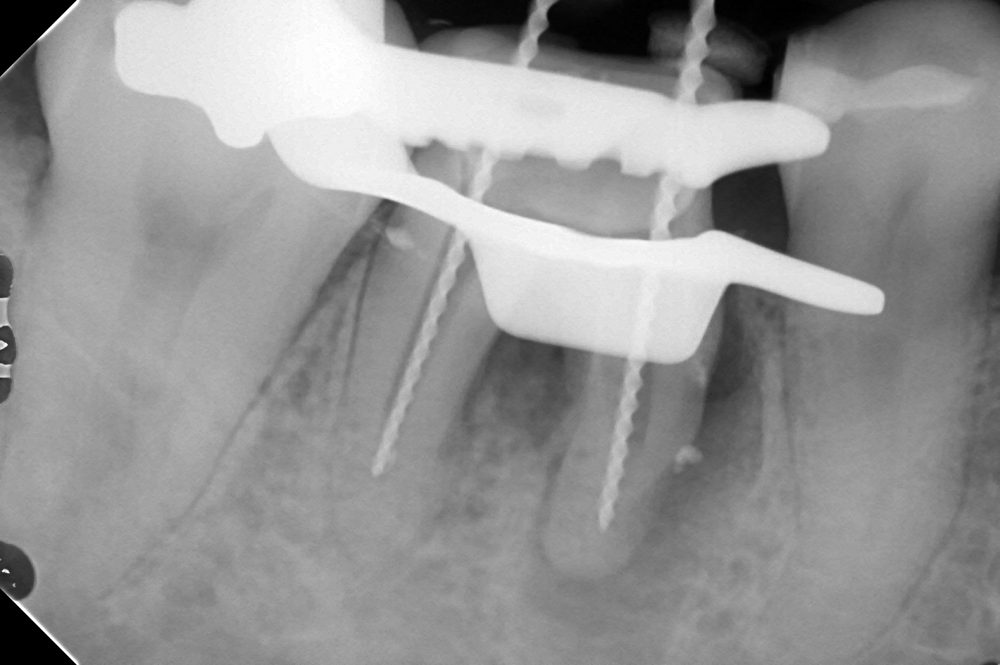

根管形成を行い、

根管充填を行いました。